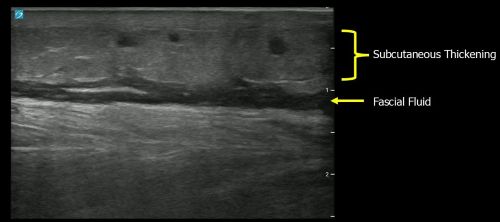

Sonographic findings suggestive of necrotizing fasciitis include:

Remember the mnemonic: STAFF (subcutaneous thickening, air, and fascial fluid)